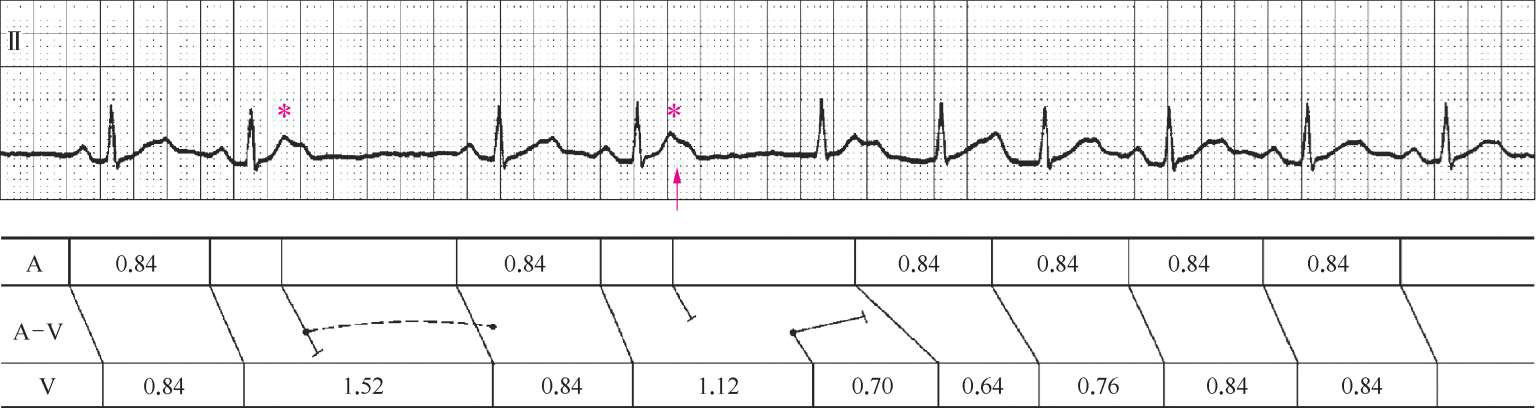

注:上图为Ⅱ导联心电图,下图为梯形图

心电图特点

1. 窦性P-QRS-T规则出现,周期840 ms,P-R间期200 ms。

2. *号所注的2个心搏为房性早搏,第1个房性早搏未下传形成1 520 ms的长R-R间期,第2个房性早搏后800 ms出现室上性QRS波群,R-R间期为1 120 ms,随后窦性心律的P-R间期为400 ms、300 ms及200 ms。

心电图分析

1. 2个房性早搏产生2种不同的心电图表现,临床上不少见。

2. 图1-2-5箭头所指的房性早搏后800 ms出现室上性QRS波群,R-R间期为1 120 ms,其后窦性P-R间期延长至400 ms,然后逐渐恢复正常,这是因为周长1 120 ms的室上性QRS波群干扰了正常窦性节律的下传,形成倒文氏现象,这在干扰中非常常见,临床上无意义。而周长为1 120 ms的室上性QRS波群性质有讨论价值。① 交接性逸搏:由于房性早搏未下传心室,被动出现逸搏,频率54次/分。② 房室结双径路:激动通过慢径路下传,P′-R间期800 ms。

3. 图1-2-5出现的现象比较支持早搏未下传心室,被动出现交接性逸搏,其理由如下。

(1) 房性早搏未下传心室出现交接性逸搏是一种常见现象。

(2) 基本窦性心律的周期为840 ms,P-R间期200 ms,如果存在双径路,提示激动从快径路下传,快径路的不应期应该短于600 ms,图1-2-5第2个房性早搏与下一个窦性P波的时间间隔>1 000 ms,此时快径路应该脱离不应期,P-R间期无理由延长到400 ms。

(3) 激动经慢径路下传并逆向隐匿阻滞快径路使快径路再次进入不应期,窦性激动下传时恰逢快径路的相对不应期而传导延缓。由于快径路不应期长但传导速度也快,正常心搏的PR间期是200 ms,即使快径路出现缓慢传导但传导时间不会大于2倍的正常传导时间。激动经慢径路下传并逆向隐匿快径路使之再次阻滞,心电图表现是激动连续缓慢下传,不会出现倒文氏现象。

4. 第1个早搏未下传心室但没有出现逸搏的可能原因是早搏隐匿性地夺获了房室连接处,使连接处节律重整后移,窦性激动得以正常下传。

因此综合上述分析,图1-2-5中箭头所指处应为倒文氏现象,由房室交界处干扰造成。

心电图诊断

1. 窦性心律。

2. 频发房性早搏均未下传心室。

3. 偶发房室交接处逸搏。